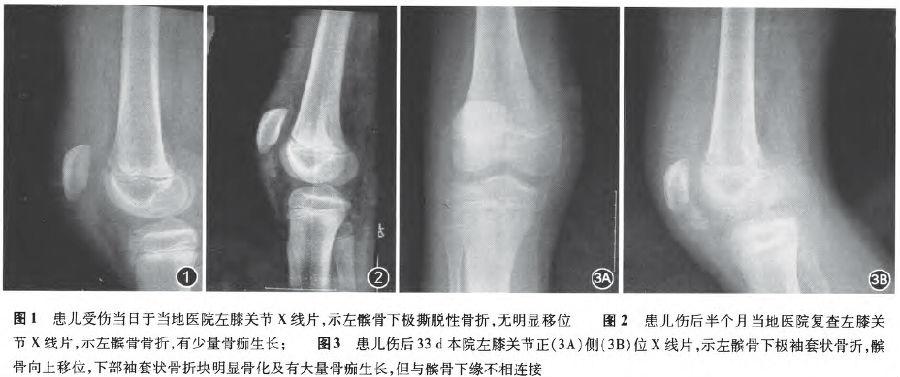

髌骨向上移位,下部袖套状骨折块明显骨化及有大量骨痂生长,但与髌骨下

髌骨骨折骨痂形成图片

髌骨骨折长骨痂图

骨折后骨痂形成图片

骨痂生长过程图

骨痂生长过程

长了骨痂的x光片图